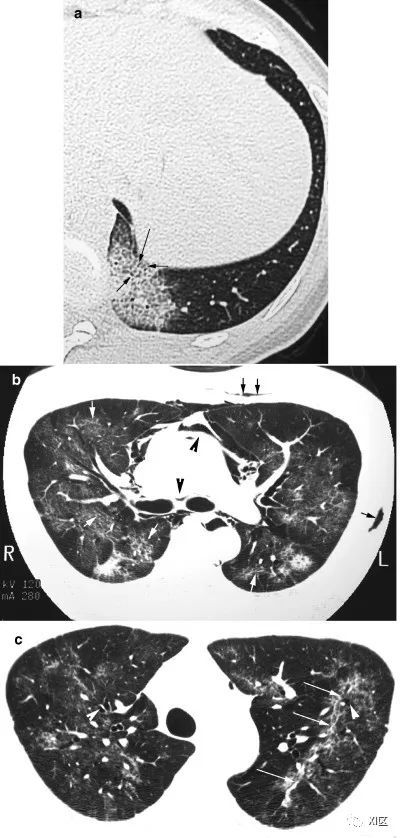

在下面的案例中,人类博卡病毒的感染胸部X线表现为弥漫性双侧斑片状实变影和GGO,CT上表现为沿着支气管血管束分布的斑片状实变影伴小叶间隔增厚。

图13 63岁的男子,原发性中枢神经系统淋巴瘤化疗后合并发热,诊断为人博卡病毒肺炎

(上)胸部X线片显示两肺均弥漫性不规则斑块状实变(箭)和GGO。在同一天获得的轴位薄层(1mm)胸部CT图像显示,沿着支气管血管束和肺部周边区域出现不规则的斑块状实变(箭),支气管壁增厚,小叶间隔增厚 (箭头),伴有少量双侧胸腔积液(*)。